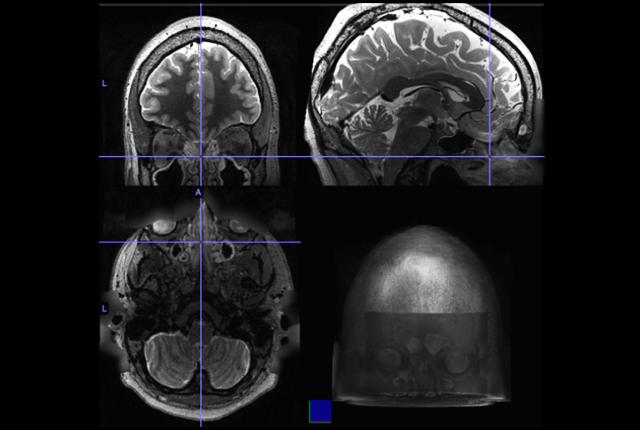

The scans enabled them to identify 22 people with moderate or severe sinus inflammation as well as an age- and gender-matched control group of 22 with no sinus inflammation. Functional MRI (fMRI) scans, which detect cerebral blood flow and neuronal activity, showed these distinguishing features in the study subjects:

- decreased functional connectivity in the frontoparietal network, a regional hub for executive function, maintaining attention and problem-solving;

- increased functional connectivity to two nodes in the default-mode network, which influences self-reference and is active during wakeful rest and mind-wandering;

- decreased functional connectivity in the salience network, which is involved in detecting and integrating external stimuli, communication and social behavior.

The magnitude of brain-activity differences seen in the study group paralleled the severity of sinus inflammation among the subjects, Jafari said.

“The participants with moderate and severe sinus inflammation were young individuals who did not show clinically significant signs of cognitive impairment. However, their brain scans told us a different story: The subjective feelings of attention decline, difficulties to focus or sleep disturbances that a person with sinus inflammation experiences might be associated with subtle changes in how brain regions controlling these functions communicate with one another,” said Simonyan.